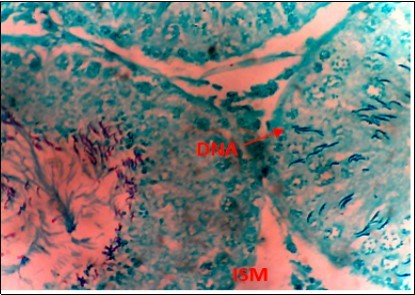

Figure 4.Diabetic Control (DC) X400 – Section of testis showing scanty DNA stained with magenta colour. DNA strands are cross linked and appear in clusters

From findings in this study, irregular and distorted arrangements of DNA in all diabetic groups (Groups B, C, D, E and F) when compared with the normal control group, may have been due to displacement of sertoli cell within the germinal epithelium of seminiferous tubules. Strands of DNA were also seen arrange in clusters in diabetic groups, showing altered and defective structure which might have resulted from base free side deletion, frame shift, cross-linking and chromosomal rearrangement. The intensity of magenta colour development in Feulgen reaction for DNA demonstration was proportional to DNA concentration. There was reduced colour intensity in all diabetic groups (Groups B, C, D, E and F) when compared with the normal control. This is in line with report from Aitken and Krausz (2001). However the degree of distortion and cross-linking of DNA strand in the group of diabetic animal models placed on high dose (1000mg/kg.bw) of A. polytricha which may be a sign of amelioration. Groups C, D and F placed on 250mg/kg.bw A. polytricha, 500mg/kg.bw A. polytricha and standard anti-diabetic drug (metformin) respectively did not show remarkable differences in terms of DNA arrangements when compared with the diabetic control group. Groups D (500mg/kg.bw A. polytricha) and group E (1000mg/kg.bw) showed visible improvement in magenta colour intensity when compared with the diabetic control group.